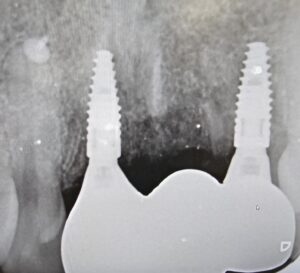

Sometimes our patients have an even more bespoke request. This particular patient had lost his upper incisor teeth many years ago. He finally decided that now was the time to have dental implants to replace his missing teeth and restore his smile. Having left the area without teeth for so many years, our patient had experienced advanced bone loss. Our CBCT scan assessment showed that he would require a large bone graft to be able to have dental implants however, it was still possible to achieve this treatment for him because he hadn’t left it too late!

Once I had successfully provided our patient with 2 dental implants and a bone graft he then had one more personal request – a very unique one! He wanted me to make his 3 replacement teeth out of gold! Now gold is actually one of the best materials to place in the mouth as it adapts almost perfectly with your own teeth and exhibits properties that enable it to adapt comfortably with your own biting pressures. Despite this, it is rare for a patient to request this however, at our clinic we look forward to providing each of our patients with the unique care and smiles they deserve.